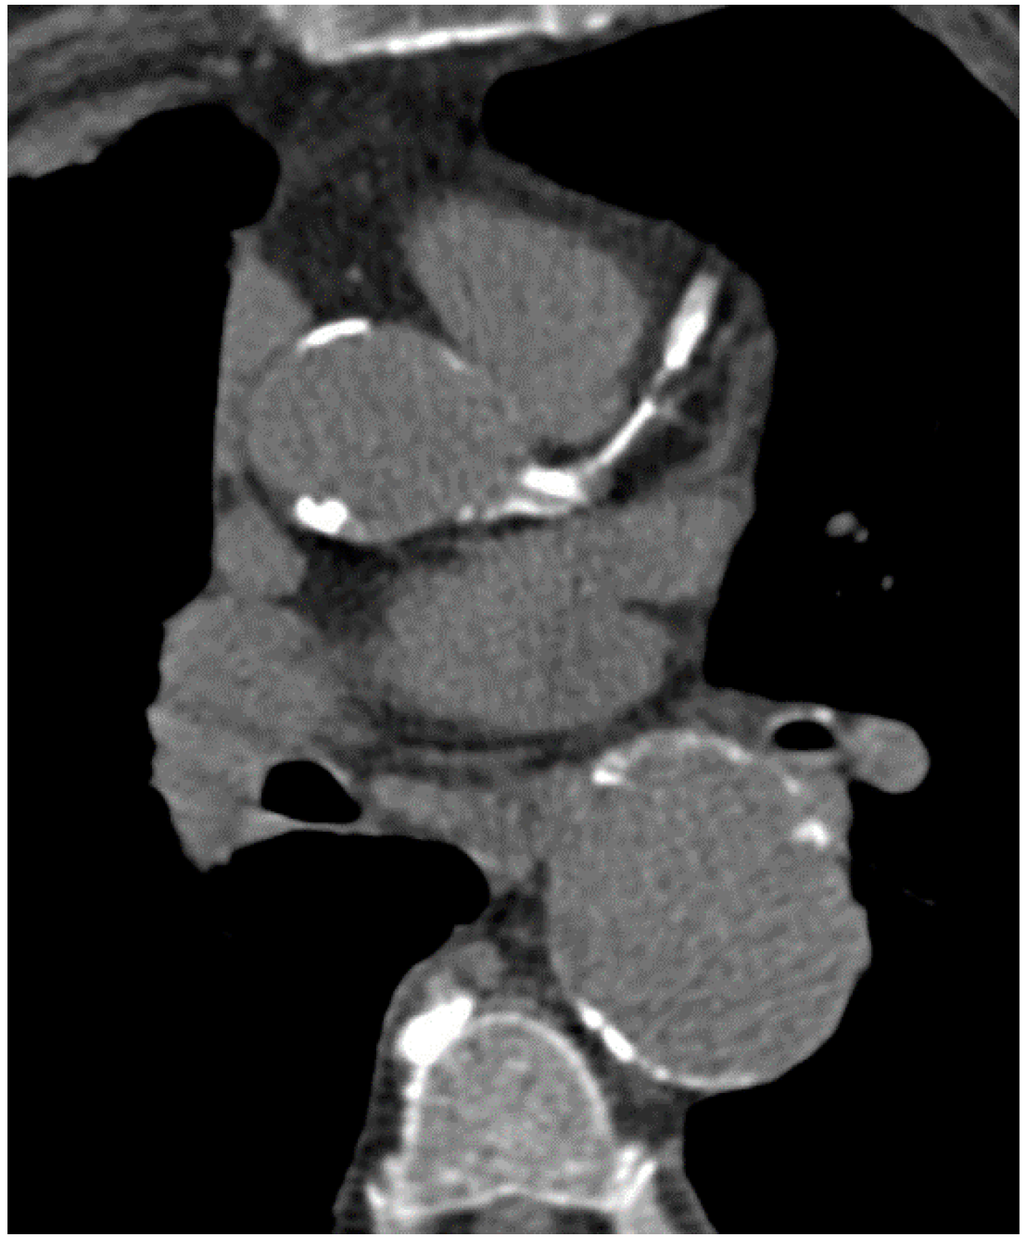

Coronary artery calcium scoring Its practicality and clinical utility Calcium Build Up In Main Artery coronary artery disease is caused by the buildup of fats, cholesterol and other substances in and on the walls of the heart. calcification happens when calcium builds up in tissue, blood vessels, or organs, causing them to harden. aortic valve calcification is a condition in which calcium builds up on the aortic valve. Plaques in the arteries. Calcium Build Up In Main Artery.

Coronary Calcium Scan Manhattan Cardiology Calcium Build Up In Main Artery a cac test, also called a heart scan, is a ct scan of your heart done with a multidetector ct (mdct) that takes. a ct scan of the heart can show calcium deposits and blockages in the heart arteries. a coronary artery calcium score is a measure of how much calcified plaque (calcium) is in the walls. Calcium Build Up In Main Artery.